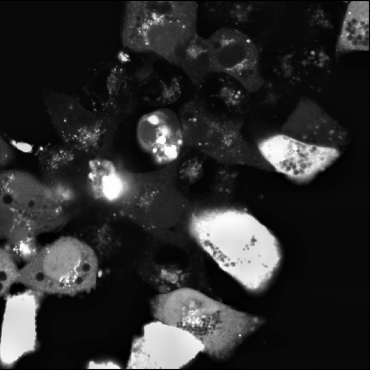

Stratifying the data by the six projection methods (Figure 2) linked abnormally high BRISQUE values to images processed with PDP. These images also showed generally higher PIQE and NIQE scores than the other techniques. Qualitative inspection of images with the worst BRISQUE scores confirmed corruption (Figure 3(c)). As a result, PDP images were unusable for GT annotation and were discarded from further analysis.

To complement the quantitative analysis of NR-IQA scores and assess whether the chosen image quality metrics effectively correlate with changes in the visual quality of our microscopy images, we conducted a complementary qualitative analysis on an exemplary subset of the HL-1 dataset (N = 18). PIQE, NIQE and BRISQUE were individually sorted in ascending order to identify exemplary images scoring the closest values to the minima, median and maxima identified in Table 2. Results of this analysis are summarised in Figure 3. PIQE assigned the highest values (i.e., P = 79.07 and P = 79.76) to images characterised by high levels of blur (Figure 3c), penalising decreases in image sharpness and losses of fine details over other signs of image quality deterioration, including the high salt and pepper noise and low brightness observed in high and median quality images for PIQE (Figure 3b). Differently, NIQE and BRISQUE were shown to penalise images that were substantially degraded by the specific preprocessing pipeline applied, primarily images belonging to the PDP group, associated with the highest values for all three metrics (Figure 2). Both NIQE and BRISQE were proven sensitive to alterations of the original images, leading to the generation of artefacts introduced by the preprocessing pipeline and previously not observed within the raw frames. Examples of these alterations are visible from the exemplary median quality images reported for the two metrics (Figure 3b). NIQE was also shown to penalise low image contrast, considering images characterised by high foreground-to-background contrast of higher quality than images characterised by low brightness and low illumination variability between cellular and background structures.